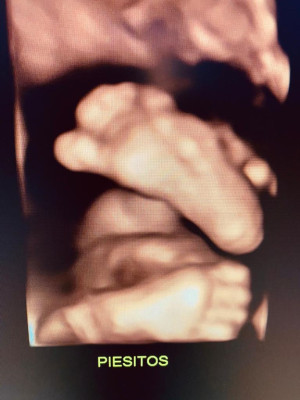

Atención de parto

Envíado por Dra. Erika Lissette Palacios